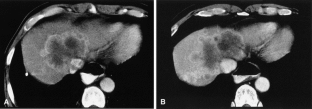

Fig. 3.